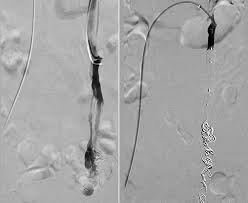

First described by Richet in 1857 the symptoms of chronic dull pelvic pain pressure and heaviness are often a result of dilated tortuous and congested veins produced by retrograde flow through incompetent valves in ovarian veins 39 41 Fig 18. Pelvic congestion syndrome PCS is characterized by chronic pelvic discomfort exacerbated by prolonged standing and coitus in women who have periovarian varicosities on imaging studies. It is thought to be caused by problems with the veins in the pelvic area.

Pelvic congestion syndrome is a chronic condition that affects women and men and can be a cause of chronic pelvic pain. Yet getting to the point of that procedure or others if you choose laparoscopy or hysterectomy is a long hard journey on its own. Procedures like pelvic vein embolization can alleviate pain with up to 85 success rate. Symptoms of Pelvic Congestion Syndrome. Chronic pelvic pain is defined as non-cyclic pain lasting greater than six months. Pelvic congestion syndrome is a chronic condition that affects women and men and can be a cause of chronic pelvic pain. This leads to blood and lymph fluid becoming stagnant or congested. After a physical examination a Pap test to rule out cervical cancer and routine laboratory bloodwork a cross-sectional imaging study is obtained to be certain that there is not a pelvic tumor. Pelvic congestion syndrome is a condition that causes chronic pelvic pain.